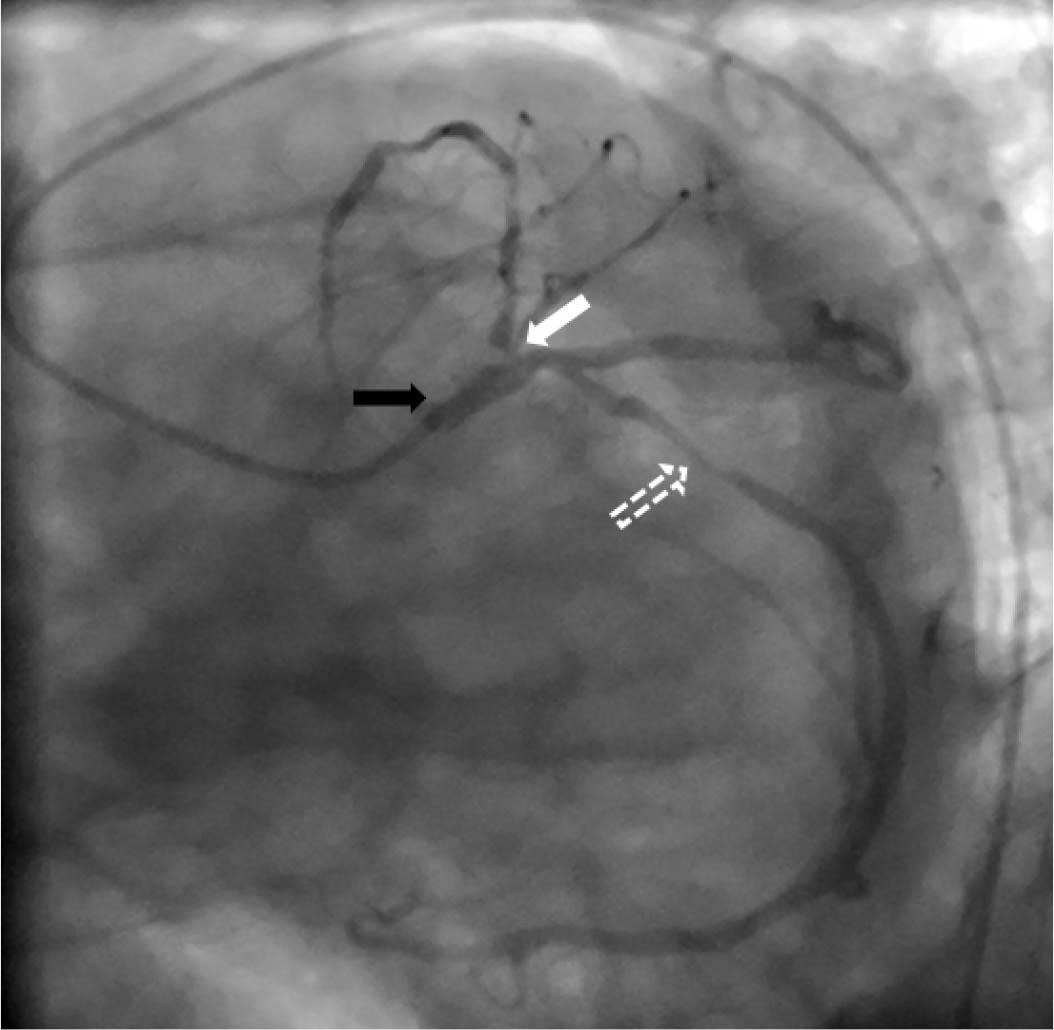

Figure 3